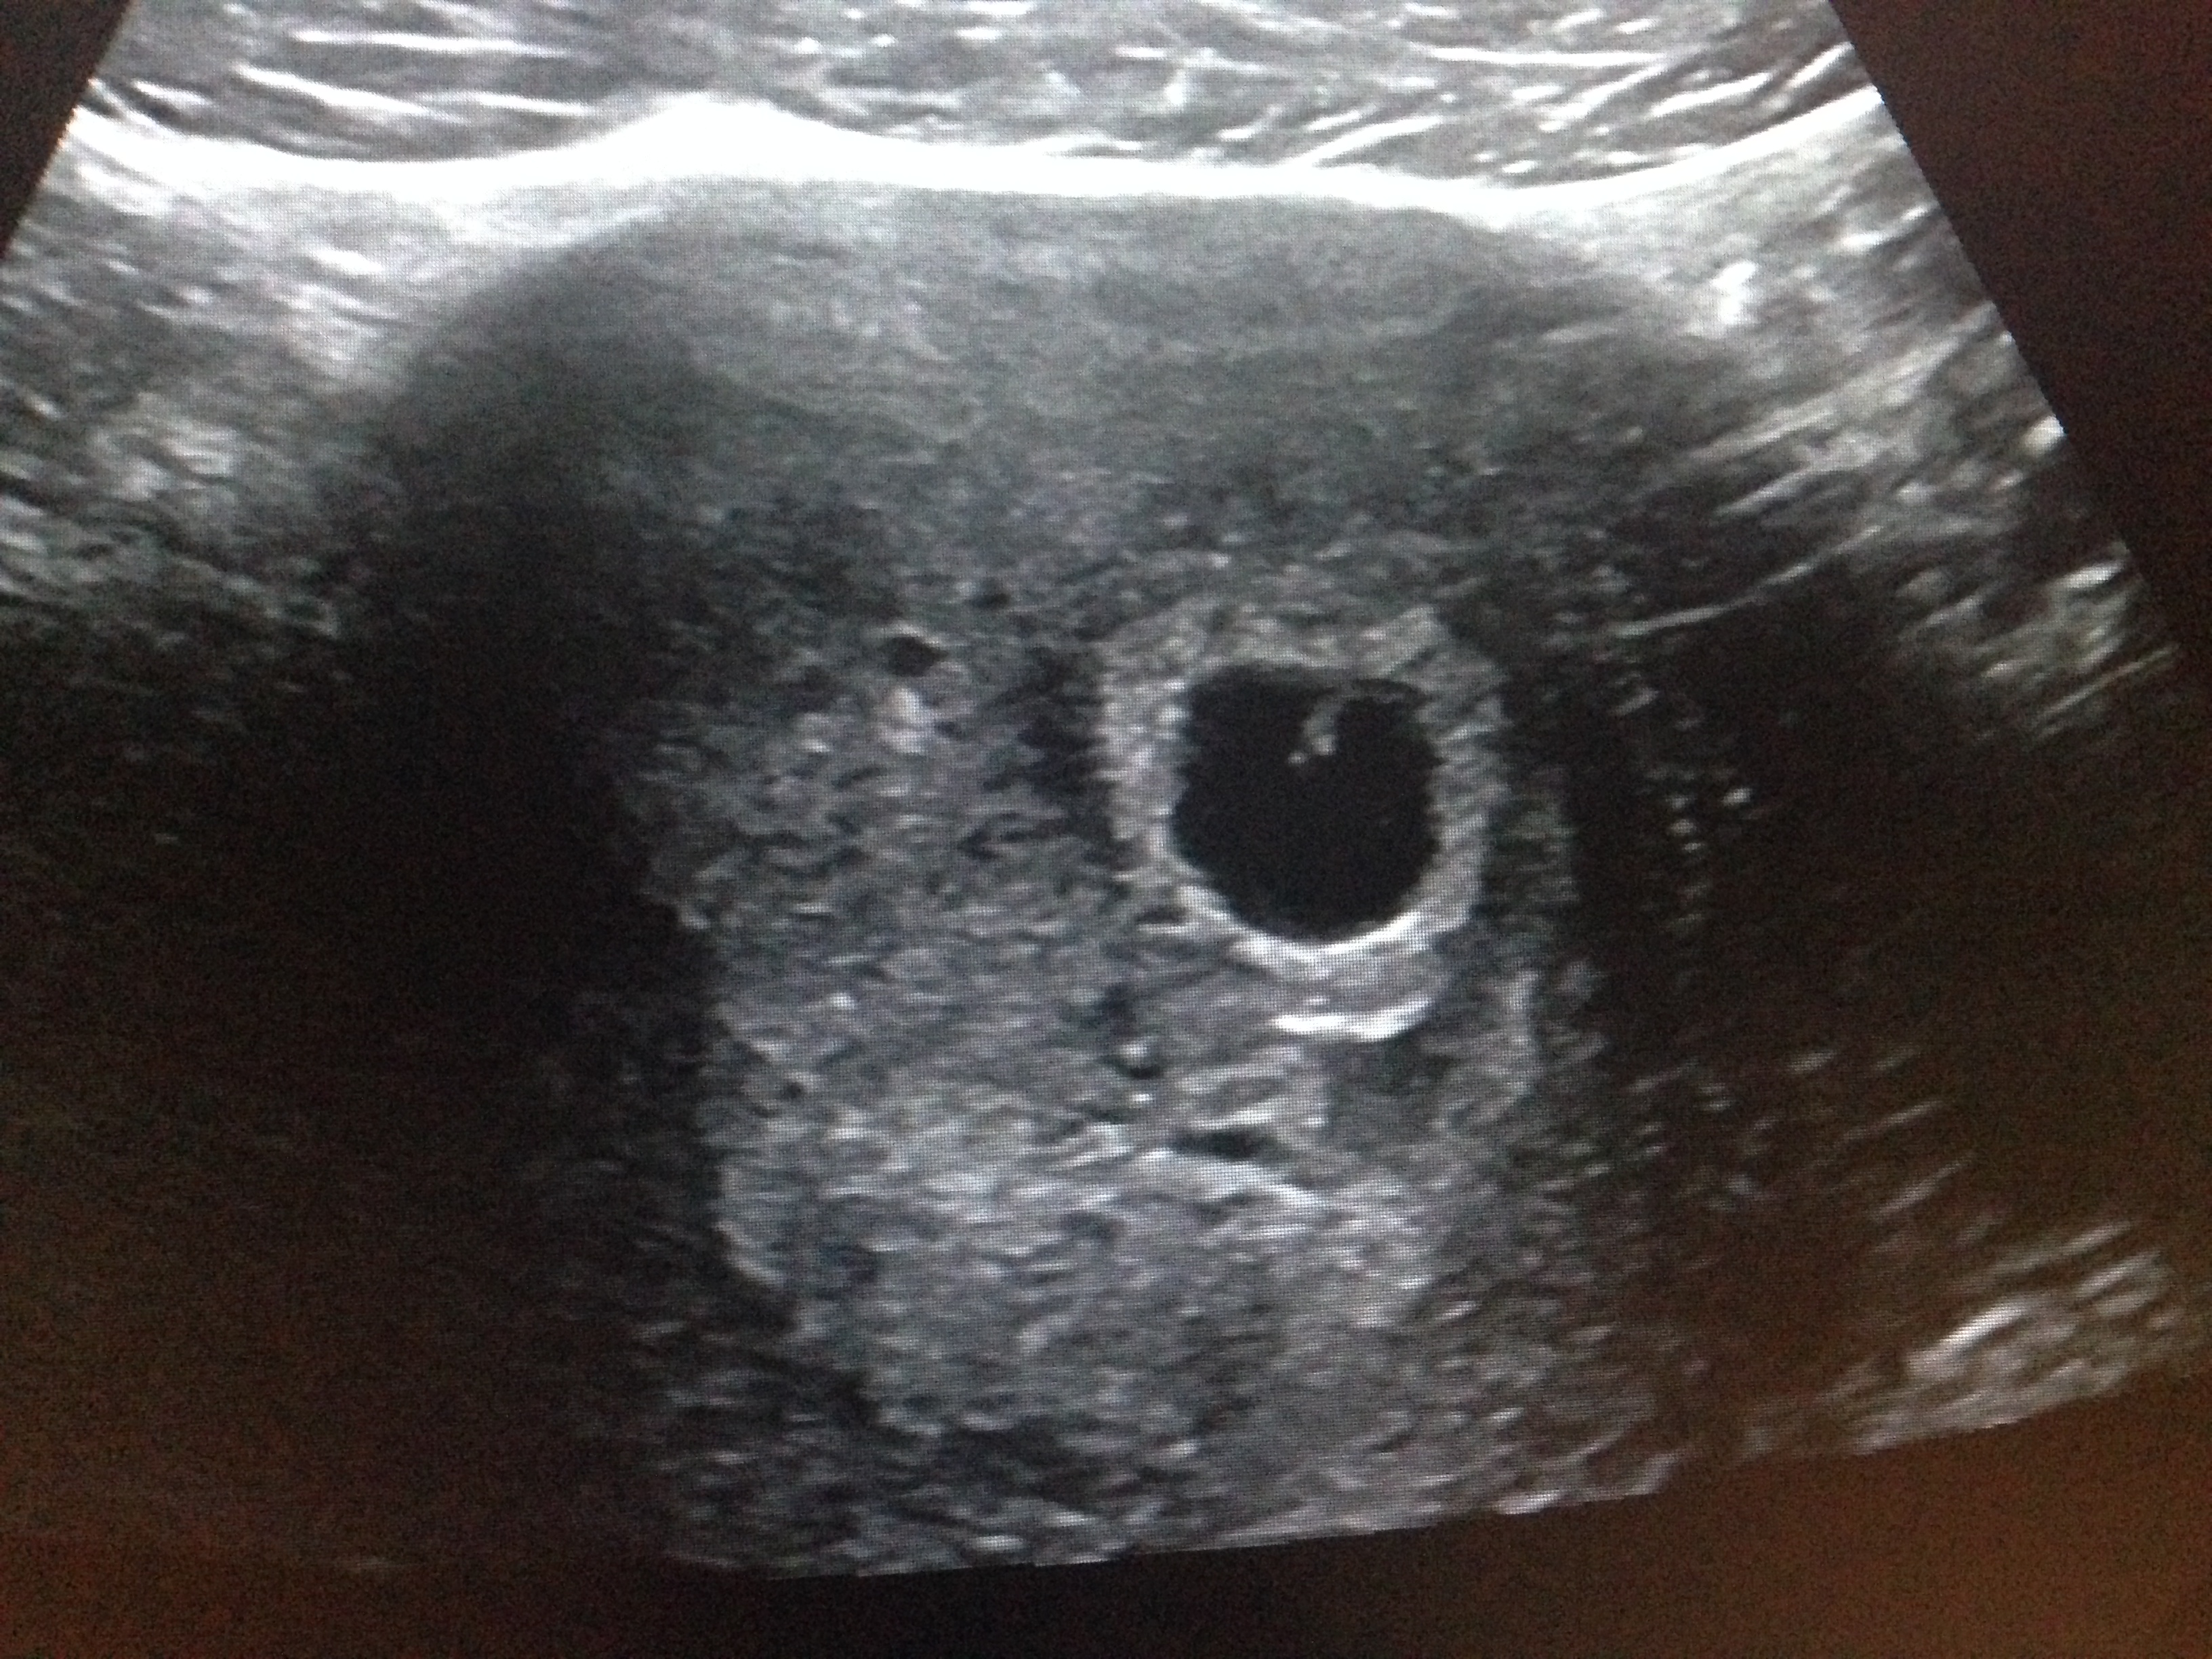

Og dere – jeg har faktisk smugkikket på lille allerede! Haha, jeg trodde ikke det var mulig å se noe som helst på utvendig ultralyd allerede i uke 6, men tror du ikke jeg fikk det til likevel. La meg presentere – lille bølle! Uke 6 + 2. Bildet er tatt av mor selv, magen måtte trekkes litt inn og ultralydproben moses godt ned i vevet, men jeg fikk et finfint bilde, selv om jeg ikke riktig kunne se noe sikkert hjerte så ser det sånn passelig ut med tanke på hvor lang jeg er på vei. Jubel!